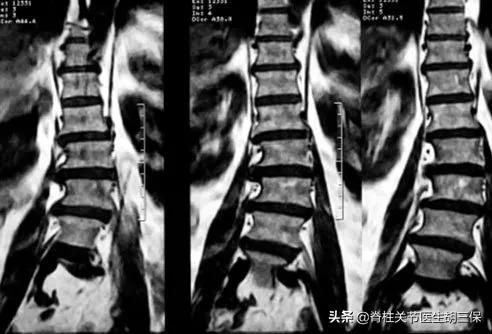

誤區:椎間盤滑脫需要手術

超過 70% 的情況下,背痛的原因是未知的。即使測試確認磁碟已損壞,您也可能不需要手術。MRI 研究表明,當椎間盤突出(凸出、破裂或突出)時,受損的椎間盤區域通常會在一段時間後自行改善。六週後,90%的椎間盤滑脫會逐漸好轉。大多數專家建議第一步不進行手術治療。如果使用更保守的治療後背痛沒有改善,則可能會建議進行手術。

誤區:X 射線、MRI 總能找到原因